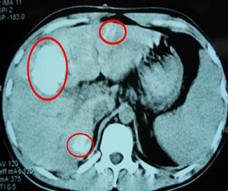

患者情況:肝細(xì)胞性肝癌,術(shù)后復(fù)發(fā),右肝內(nèi)多個(gè)病灶。治療方案:瘤內(nèi)注射今又生1×1012VP/次/周,共8周,同時(shí)聯(lián)合肝動(dòng)脈化療栓塞(TACE),1次/月,共2次。下圖示:左側(cè)上下兩圖為治療前,CT示血管豐富;右側(cè)上下兩圖為治療一個(gè)療程后,碘油均勻沉積,腫瘤血供減少。

治療前

治療后